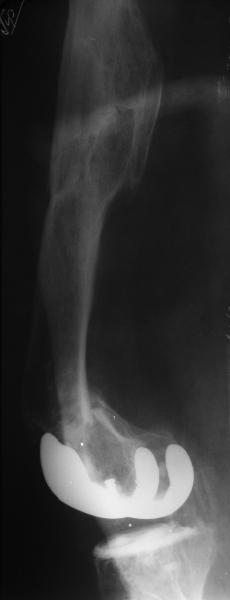

Глубокоуважаемые коллеги, Мужчина 41 года поступил с повторным (предыдущий в 2001 г.) переломом (3-недельной давности) над протезом коленного сустава.

В 1994 множественная травма, в том числе открытый перелом надколенника, осложнившийся гнойным артритом, и на этой же стороне перелом диафиза бедра (лечили в аппарате). В 1998 г. выполнено эндопротезирование коленного сустава.Предыдущий перелом (3 года назад) лечили консервативно, сросся при неустраненном смещении дистального блока бедра кзади ~ на 1 см.Амплитуда движений в коленном суставе перед последним переломом была ~90 градусов. Ходил без дополнительной опоры.Снимки в приложении. Какие будут предложения по поводу оперативного лечения в нынешней ситуации? У нас споры между ретро- и антеградным закрытым интрамедуллярным остеосинтезом.

A male 41 years old transferred to our unit with 3 week old femoral fracture near the knee prosthesis after a mimimal fall. In 1994 he sustained multiple injury with open patella fracture (complicated with septic arthritis), and ipsilateral femoral shaft fracture treated by ex-fix. TKA performed in 1998. In 2001 he got a periprosthetic fracture which was treated nonoperatively and healed with ~1 cm dorsal displacement of the distal femoral block. Knee ROM prior the recent injury was about 90-95 degrees. He didn't use walking aid.Images attached. I request your suggestions regarding surgical options in the situation? We mostly discuss ante- vs retrograde closed nailing.

My concern in this case would be the deformity of the old fractures might not allow for a straight nail but might be more amenable to a locking plate; or particularly in Russia, XF.